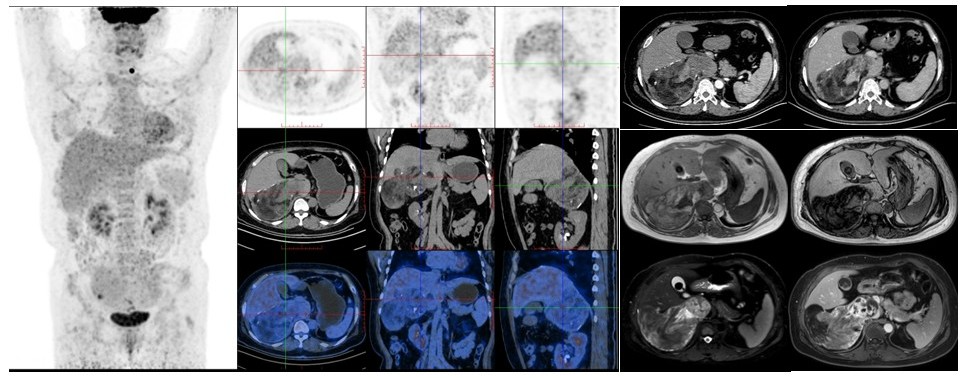

病例(1中年女性,因右肾结石于外院行腹部CT检查发现右肾上腺区肿物;增强MRI提示占T1WI同相位呈稍高/等信号反相位部分区域信号衰减T2WI呈不均匀等/高信号、DWI部分扩散受限,增强扫描病灶可见明显强化18F-FDG PET/CT示占位代谢轻度增高;(右侧肾上腺区占位)穿刺病理为髓样脂肪瘤。

病例1. 女,49岁,因右肾结石于外院行腹部CT检查发现右肾上腺区肿髓样脂肪瘤